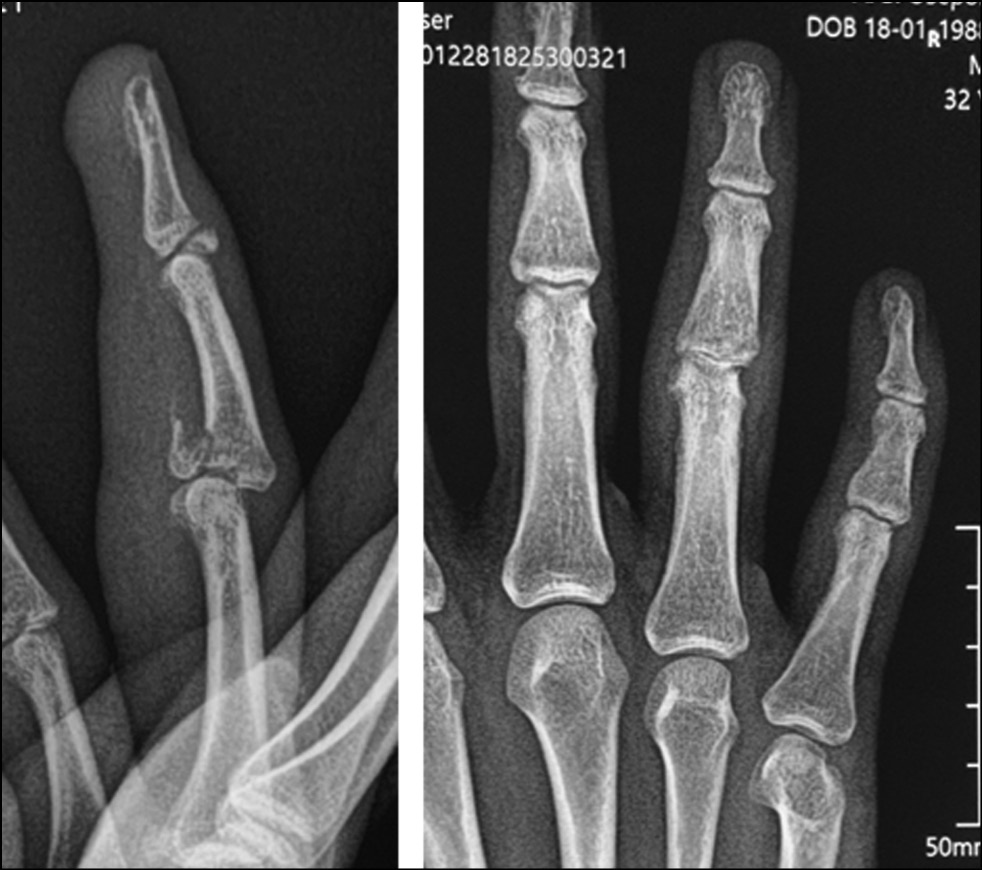

Fig. 2. X-ray picture.

Fig. 25. X-ray picture before surgery.

All patients underwent preoperative diagnostics: radiography, computed tomographic study, and clinical evaluation of the range of motion in the joint. According to the radiological and tomographic signs, the fractures of the palmar edge of the base of the middle phalanx with its dorsal subluxation, and in three cases fractures of the dorsal edge of the base of the middle phalanx with palmar subluxation, accompanied by failure of the central bundle of the tendon of the common extensor tendon of the finger, were determined as malunion fractures. According to the Eaton classification, they are categorized as groups IIIa and IIIb. In all cases, the amplitude of movements in PIP joints was sharply limited; flexion was up to 30°. Pain syndrome at the moment of attempted flexion in the joint was assessed by patients ranging from three to four points on VAS.

During 2021−2022, 26 patients (23 men and 3 women) with fracture dislocation of the middle phalanx base of triphalangeal fingers of hand in the acute period of trauma sought care. The average age was 31 years (16–46 years). The mechanism of injury was axial direction of force (impact) with rear deviation. All patients underwent preoperative diagnosis: radiography and clinical assessment of the amplitude of motion in the joint. Avulsive (detached) fractures of the palmar edge of the middle phalanx base with its dorsal subluxation were determined by radiologic signs. According to the Eaton classification, the patients were categorized as group IIIa. In all cases, the amplitude of movements in PIP joints was sharply limited by pain syndrome. Pain syndrome at the moment of attempted flexion in the joint was from 6 to 8 points on VAS. It was decided to treat all these patients with fixation of the injured finger in the Suzuki distraction-reposition external fixation apparatus (Figs. 24−29). This apparatus was described by Y. Suzuki in 1994 and represents t system of intraoperatively modeled three Kirschner spokes connected by rubber ties [8].